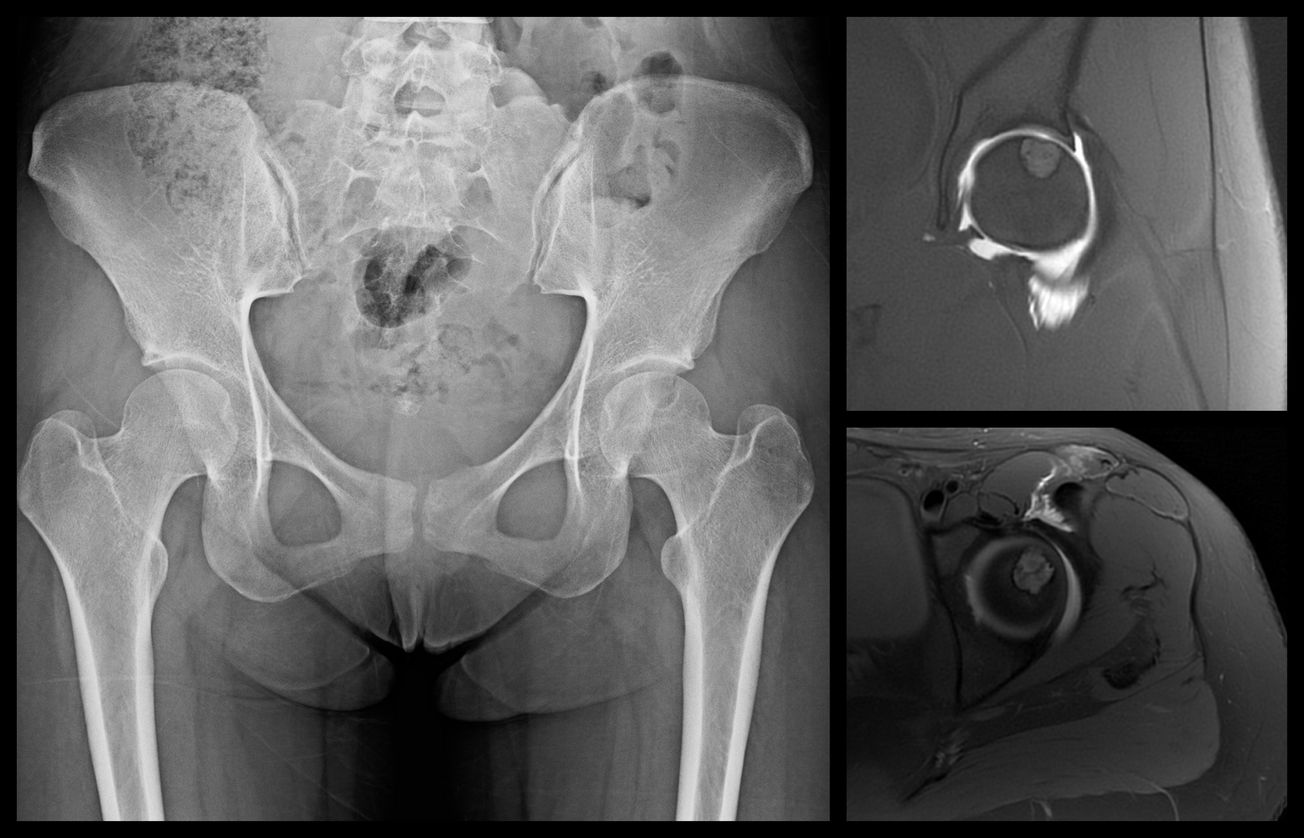

Surgical Hip Dislocation